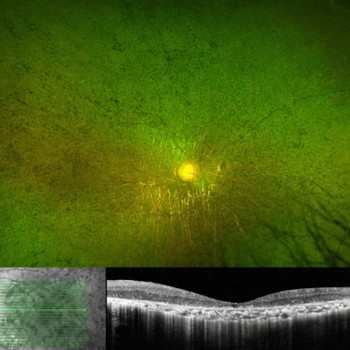

Fig 5. Optos photo and OCT of the fundus of a patient with advanced rod-cone retinal dystrophy and counting-fingers vision. The OCT shows loss of photoreceptors, but preservation of the inner retinal layers, including the retinal nerve fibre layer, which is the target for KIO-301 optogenetic therapy